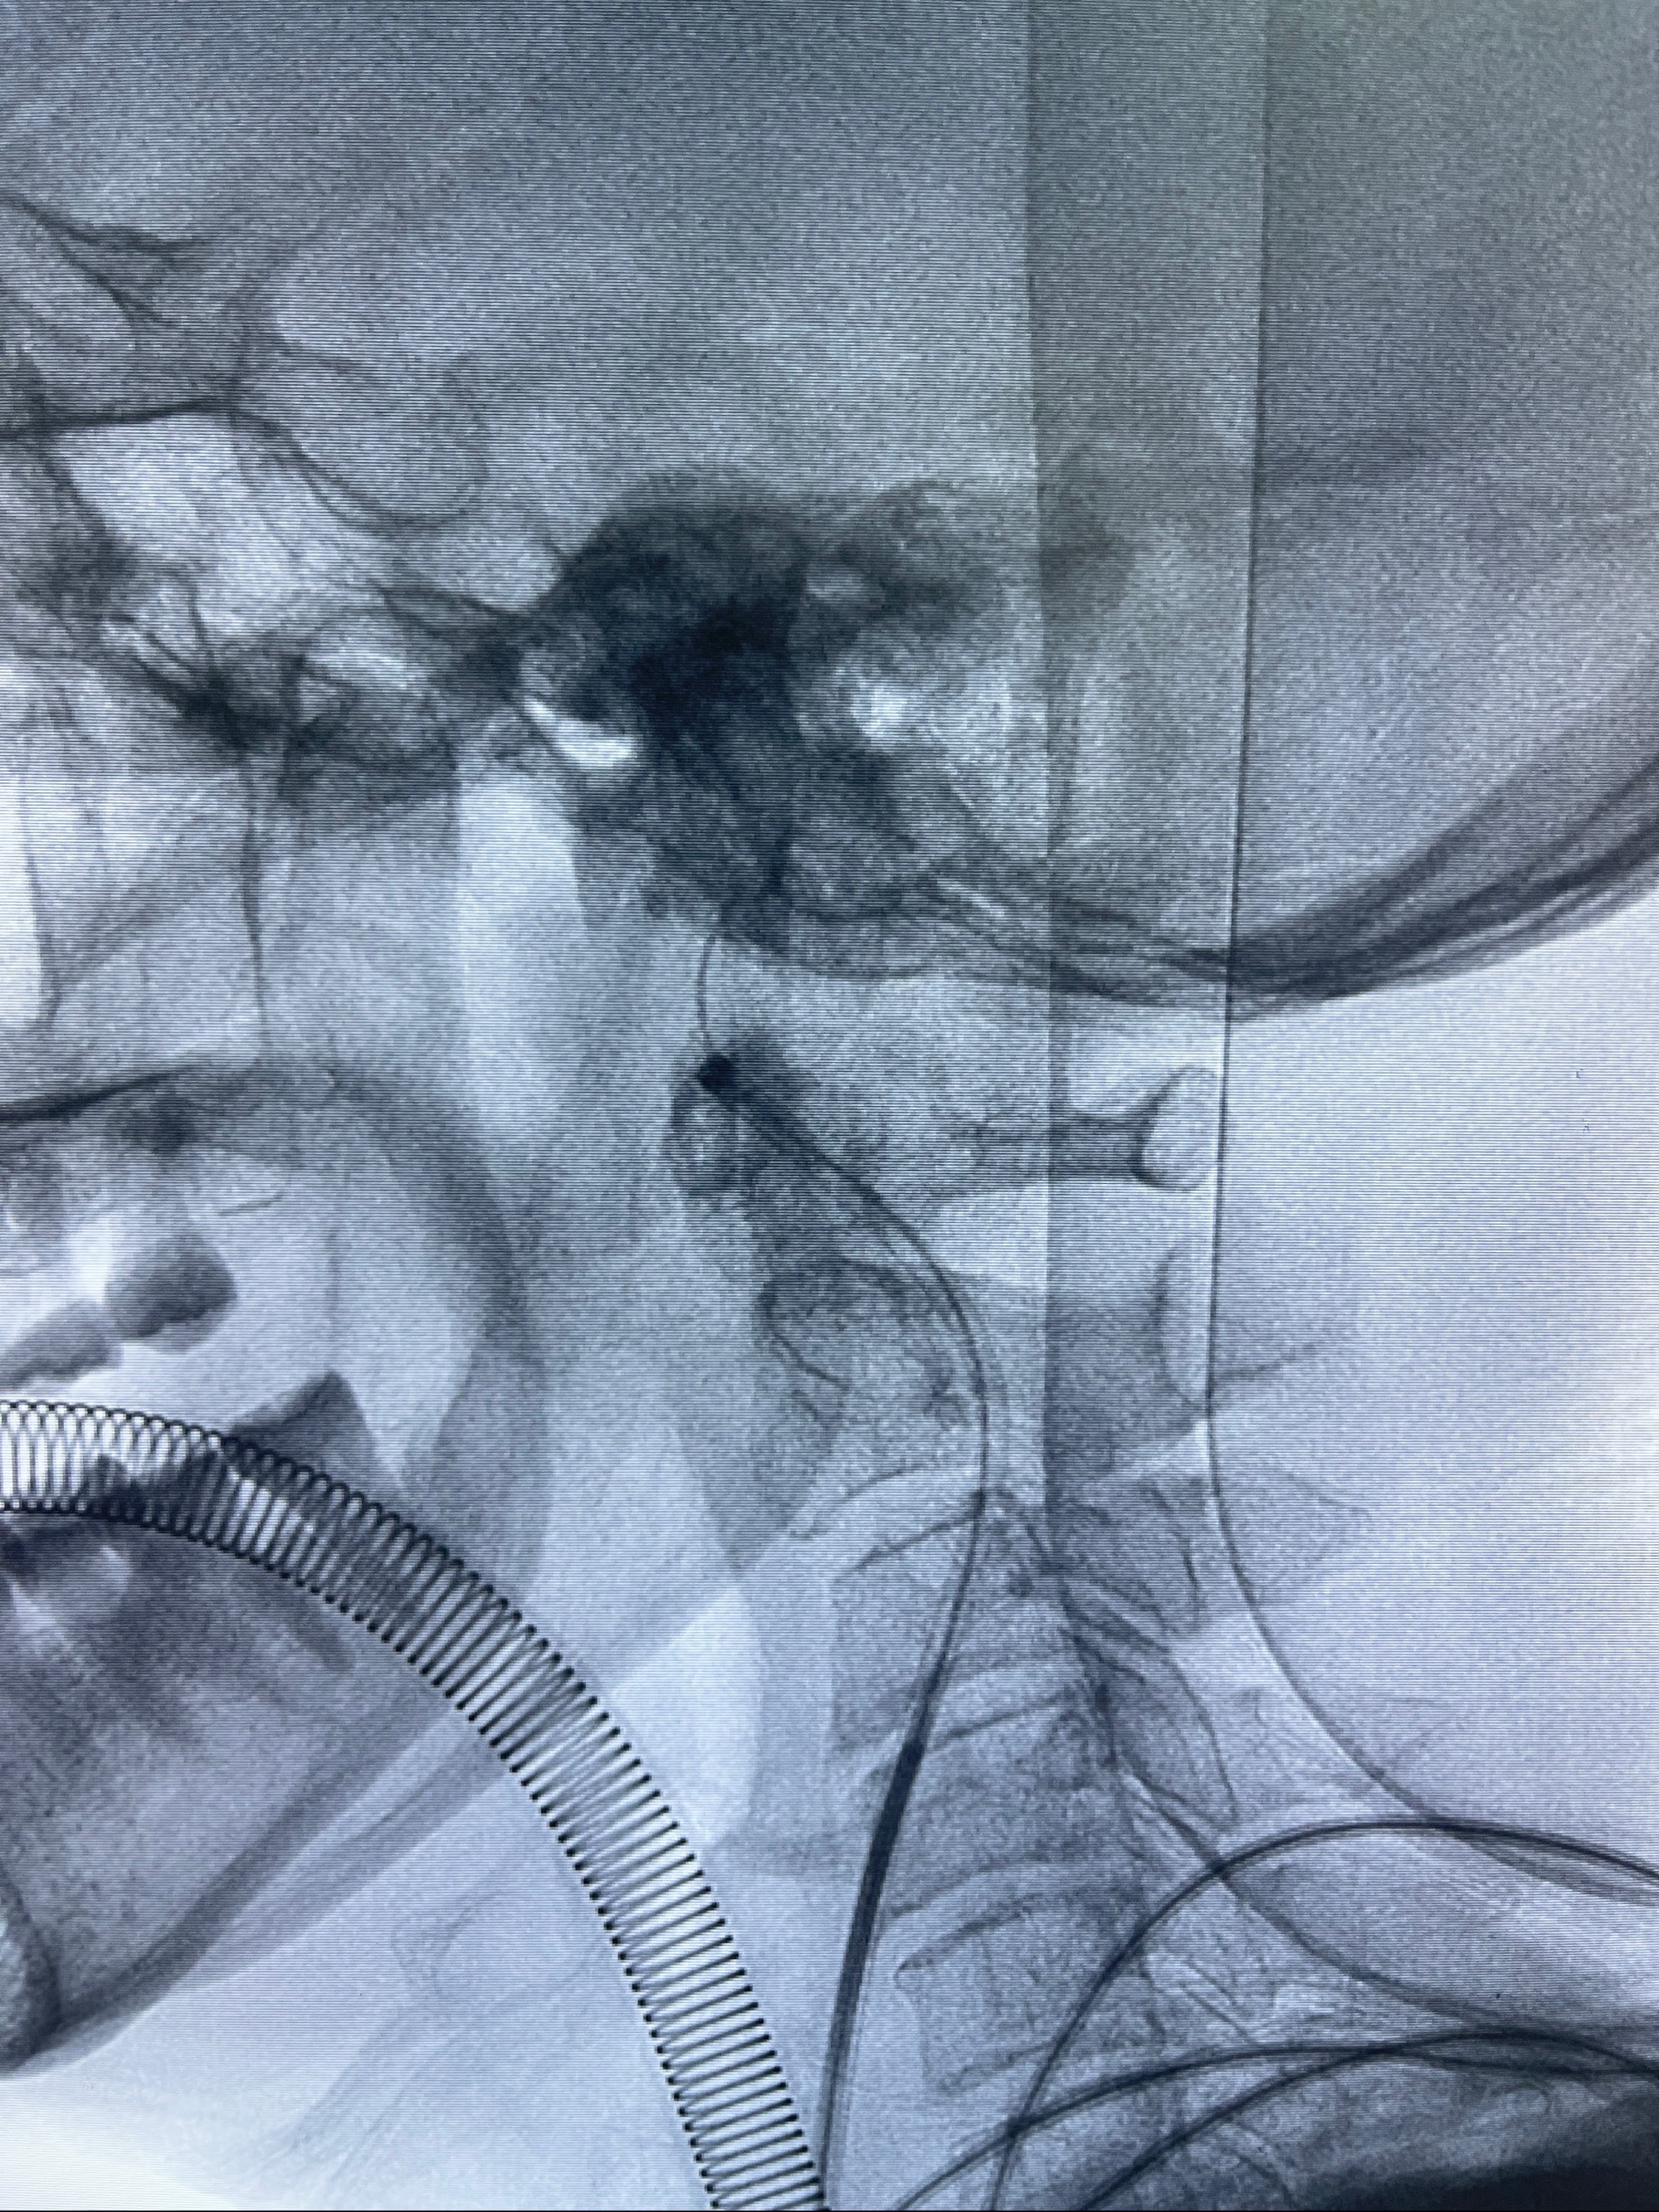

2023-08-30DSA:左侧颈内动脉眼动脉动脉瘤,约3*9.2*7.3mm大小

2023-09-06全麻下行左侧颈眼动脉瘤

密网支架辅助栓塞

- Tubridge 4.0-20mm密网支架

- 加奇微弹簧圈:7*30/6*20/5*20/2*8